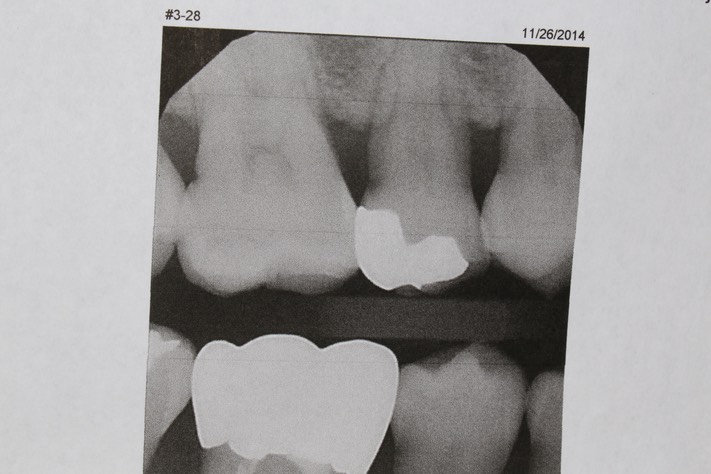

Chris Woo #4 bitewing